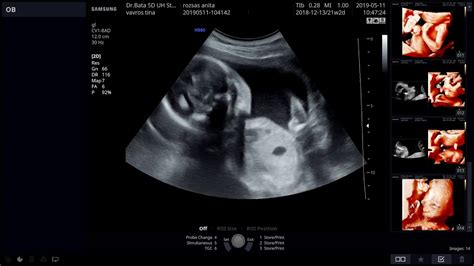

Az ultrahangos mérések pontossága kérdéses lehet, mivel apró eltérések is jelentős eltérést mutathatnak a becsült súlyban. Az orvosok sem látják mindig tisztán az ultrahang felvételeket, és nem mindenkit lehet egyformán vizsgálni. Az ultrahangon mért méretek alapján saccolják a súlyt, ami nem mindig felel meg a valóságnak.

A 30. hét környékén a magzat átlagosan másfél kilogrammot nyomhat. Azonban, ha a becsült súly kisebb, mint az átlag, az nem feltétlenül jelent problémát. Lehetséges, hogy a baba csak most kezd el rohamosabban fejlődni, vagy egyszerűen kisebb súlyú lesz a nagy átlagnál. A legfontosabb az, hogy a magzat jól fejlődik-e, és megfelelő-e a táplálása.